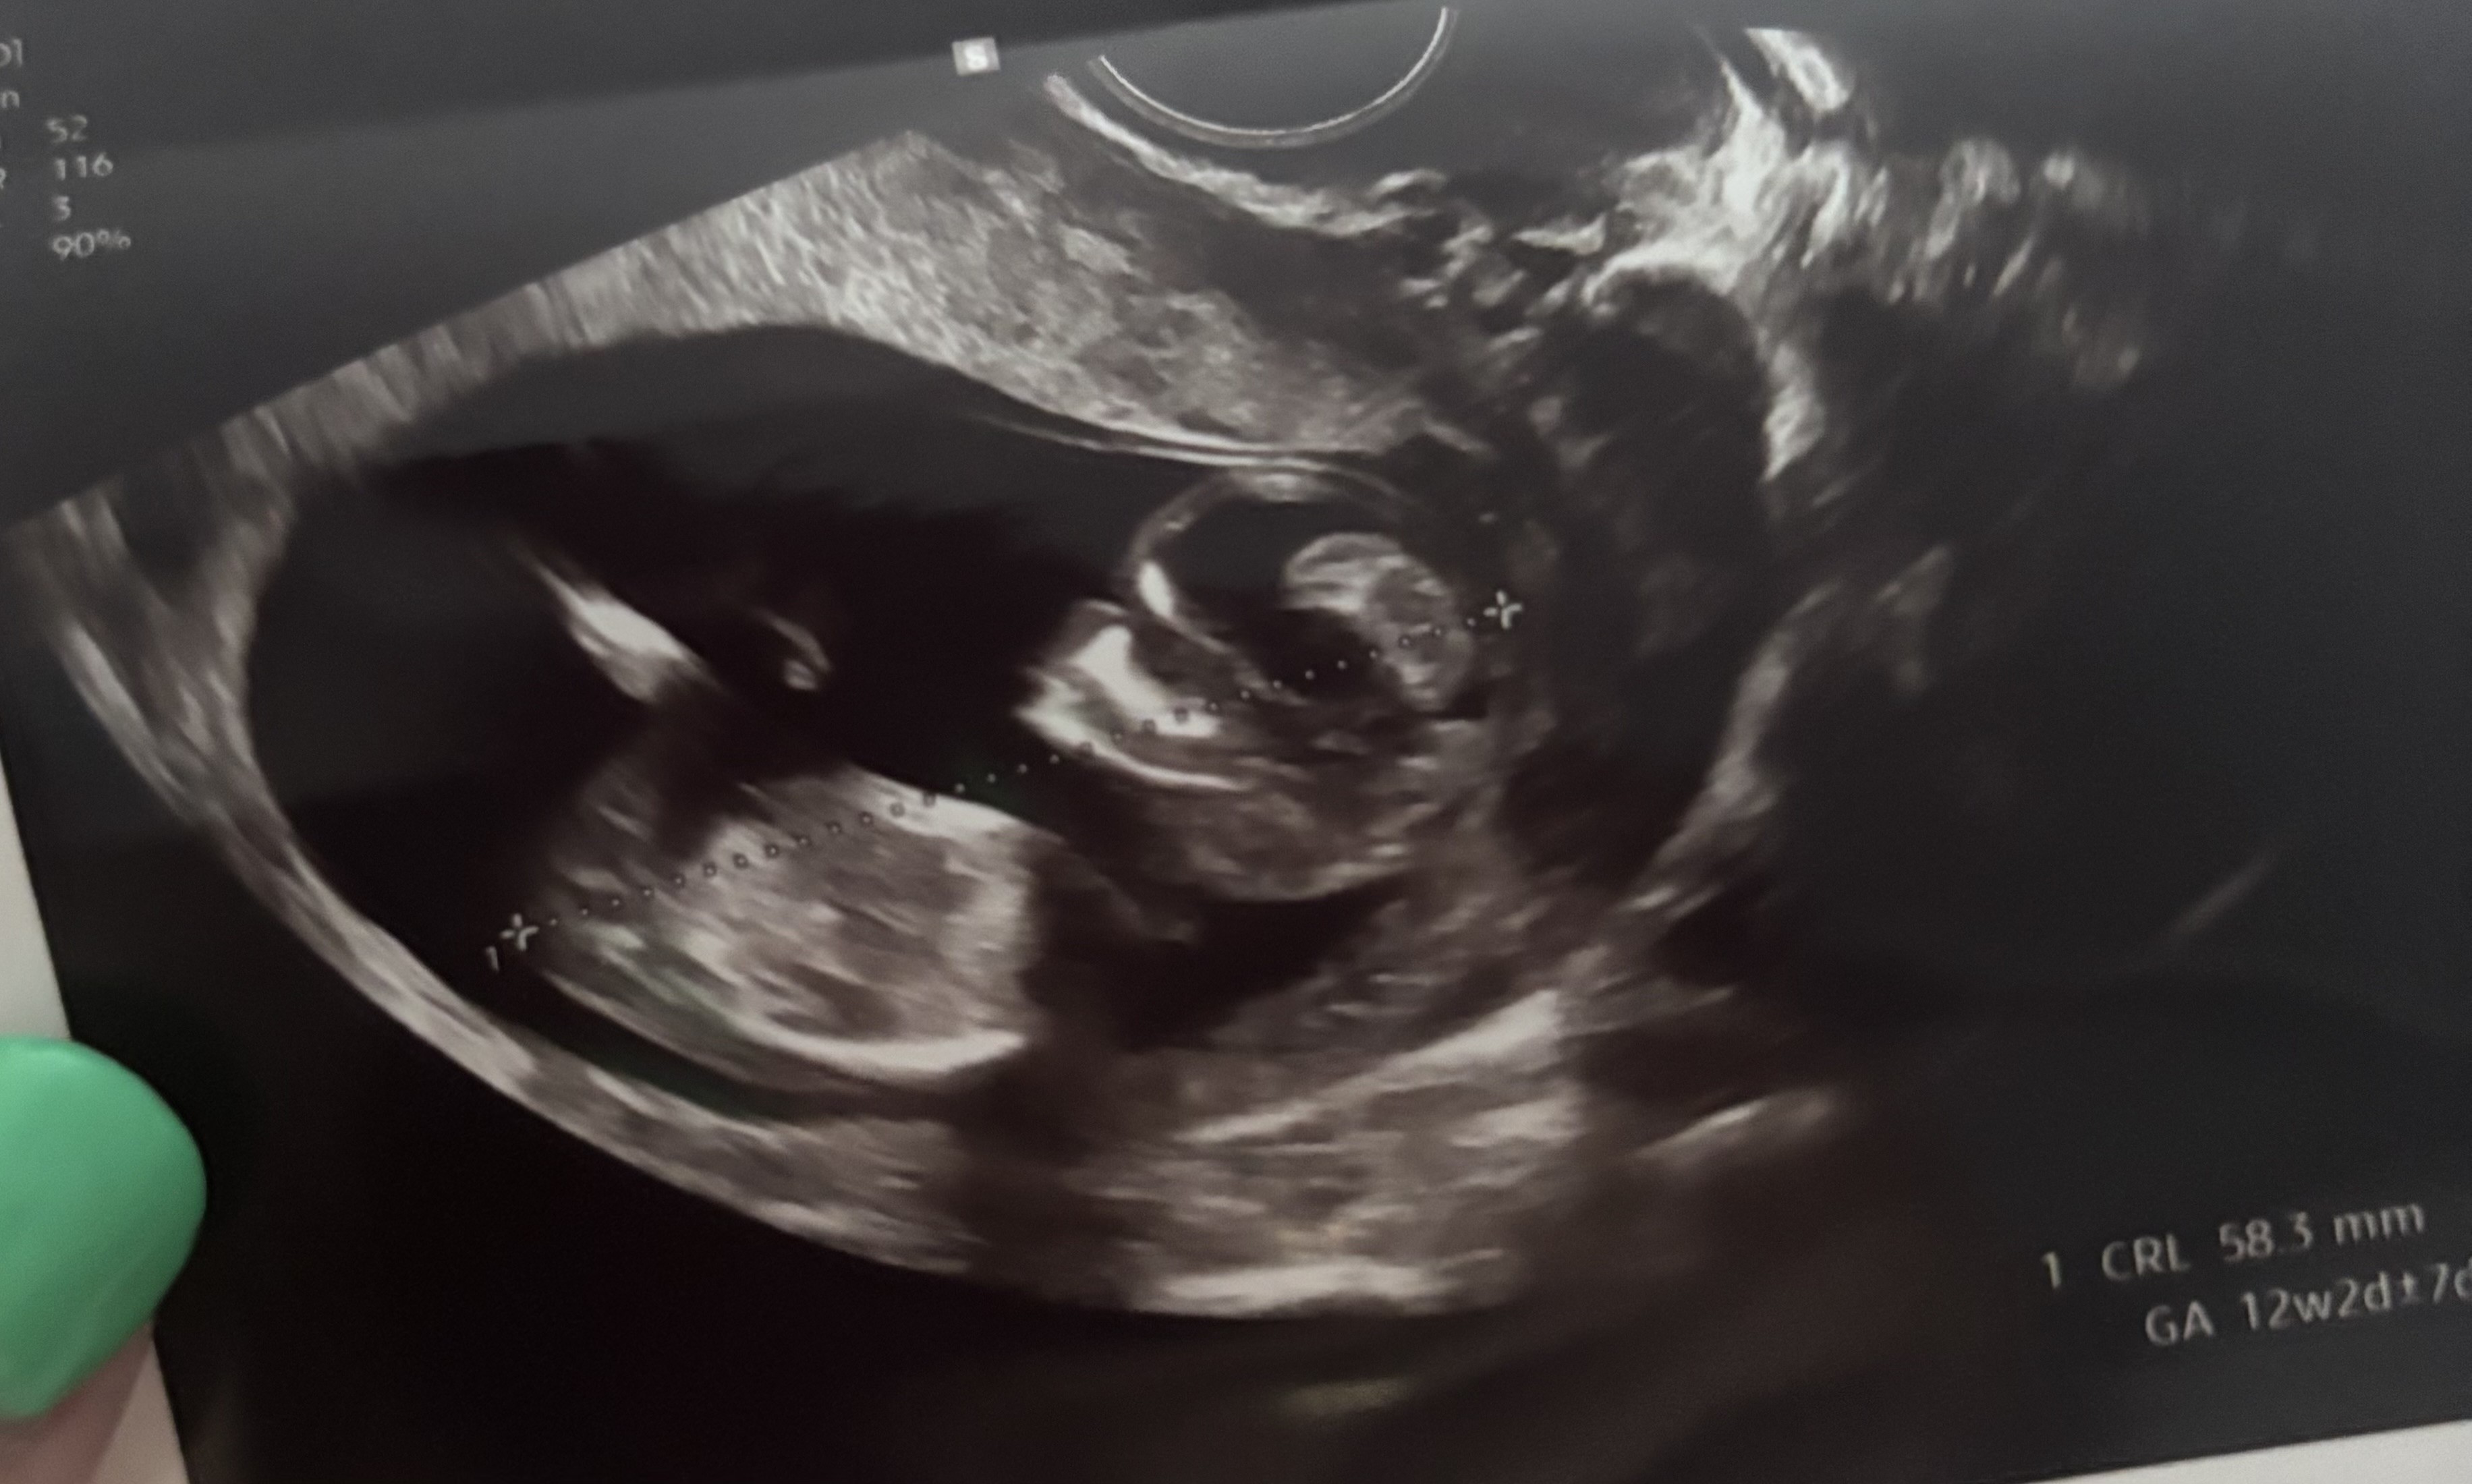

Kochana, spróbuj w chat gpt! Ja tez nie wiedzialam, dla mnie czarna magia, lekarz tylko zasugerował chłopaka, a chat gpt też twierdzi, ze chłopak po wyrostku.Dziewczyny, ja to w tym zielona, a lekarka nie chciała nic sugerować co do płci póki co ale może Wy tu coś widzicie?![]()

Ja też specjalistka nie jestem, ale jeśli mi się dobrze wydaje i dobrze lokalizuje ten wyrostek to chyba dziewczynka?? Bo jest skierowany w dół, nie odstaje do góry.Dziewczyny, ja to w tym zielona, a lekarka nie chciała nic sugerować co do płci póki co ale może Wy tu coś widzicie?![]()

Wrzucałam już do „ajaj” jak ja to mówię ale uznał że nie widać dobrzeKochana, spróbuj w chat gpt! Ja tez nie wiedzialam, dla mnie czarna magia, lekarz tylko zasugerował chłopaka, a chat gpt też twierdzi, ze chłopak po wyrostku.![]()

Ja to tylko tyle że wiem gdzie patrzeć ale nie wiem czego szukaćJa też specjalistka nie jestem, ale jeśli mi się dobrze wydaje i dobrze lokalizuje ten wyrostek to chyba dziewczynka?? Bo jest skierowany w dół, nie odstaje do góry.

Słuchaj wrzuciłam Twoje zdjęcie i wychodzi, ze dziewczynka! Trzeba dobrze sformułować pytanie.Wrzucałam już do „ajaj” jak ja to mówię ale uznał że nie widać dobrzedla mnie teraz chat gpt to w ogóle jak wyrocznia, już Google to nie używam